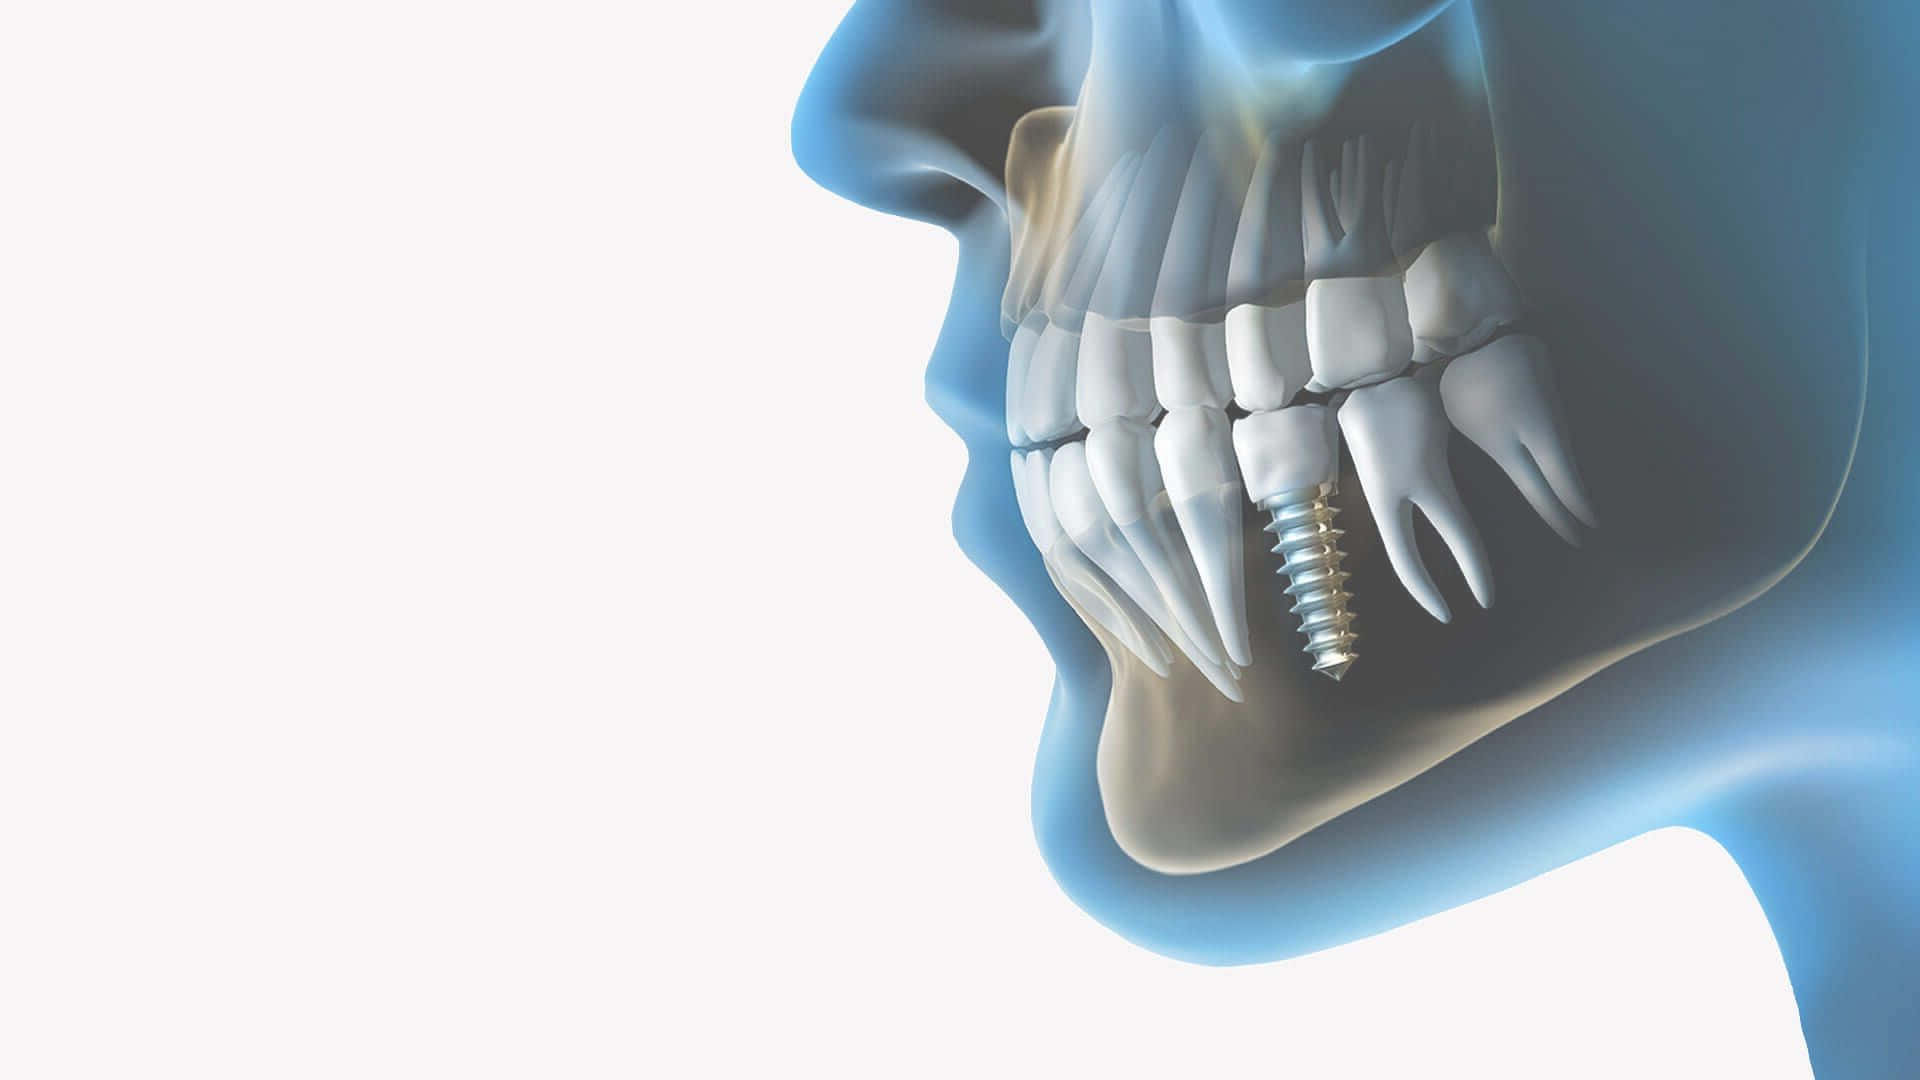

Зубы на черном фоне: Визуализация стоматологических изображений

Раздел: Необычные решения